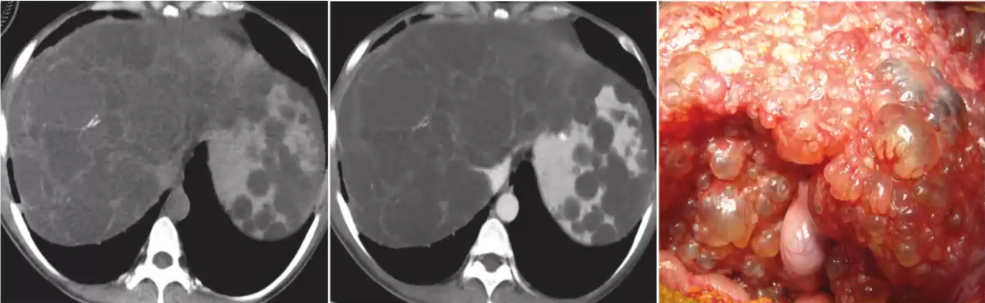

影像学表现:单发或多发、圆形、边界光滑锐利

CT:低密度影(CT值与水接近),增强扫描无强化

单纯性肝囊肿壁薄而光滑的病变,内衬立方上皮,分泌胆汁样液体,囊肿的直径<30 cm,并且可能包含多达2个隔膜